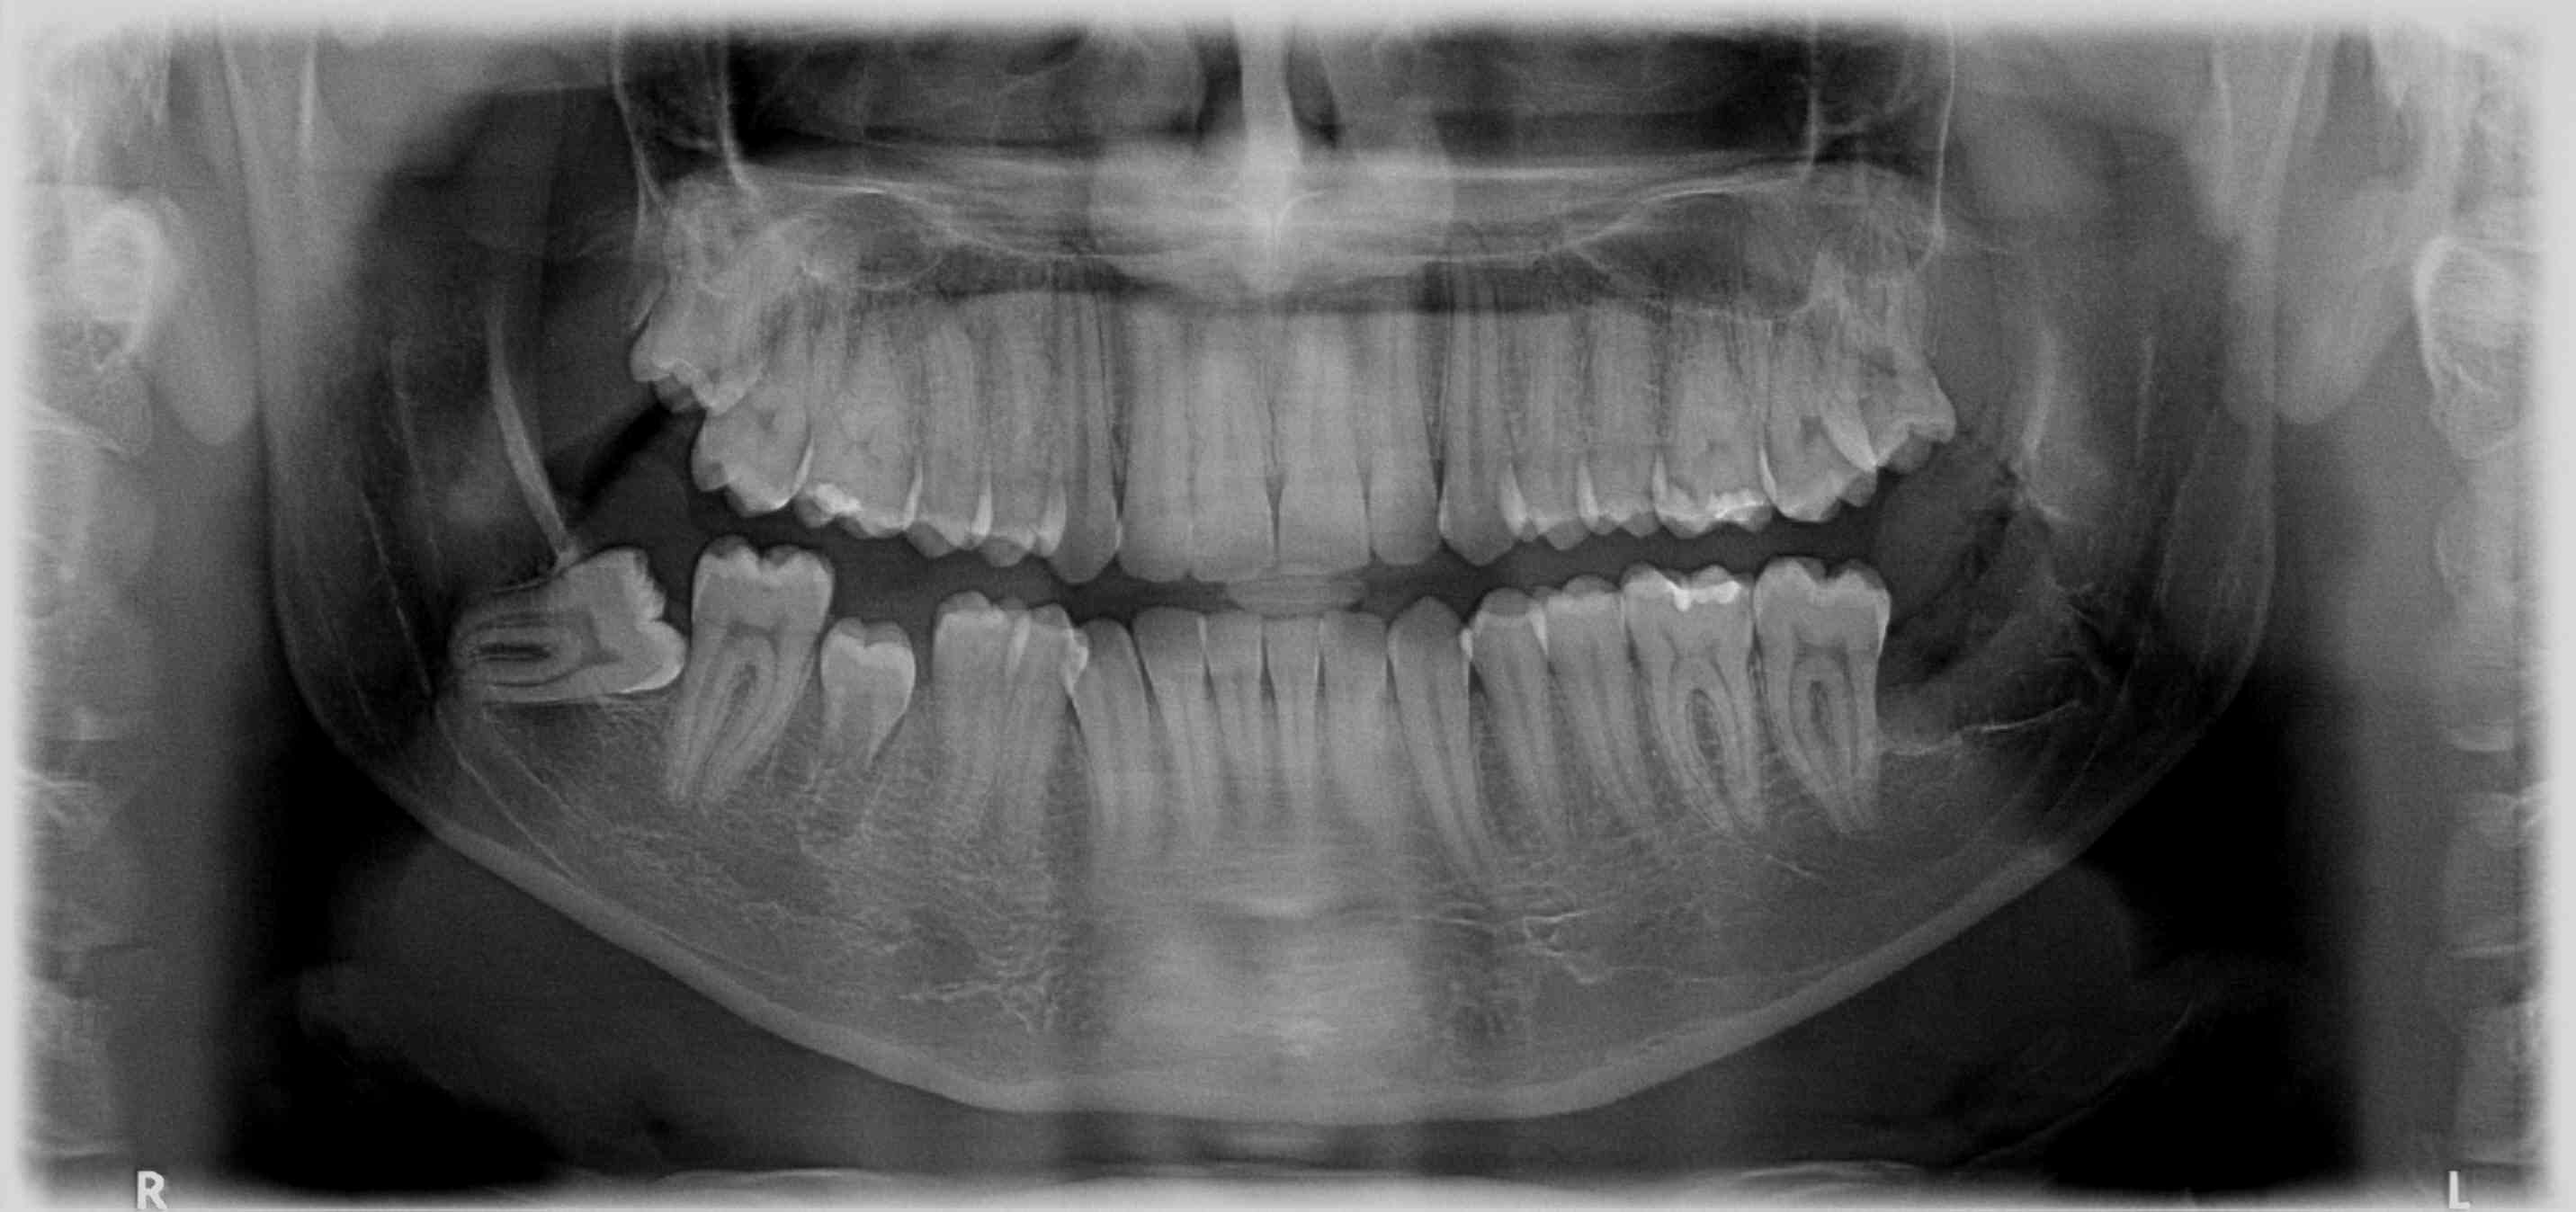

Inteligência Artificial para identificar doenças sistêmicas em exames de imagem odontológicos.

Utilizando inteligência artificial e imagens de exames odontológicos, o Gigasistêmica busca prever doenças crônicas antes mesmo dos primeiros sintomas, apoiando diagnósticos mais rápidos e eficazes.

radiografia panorâmica